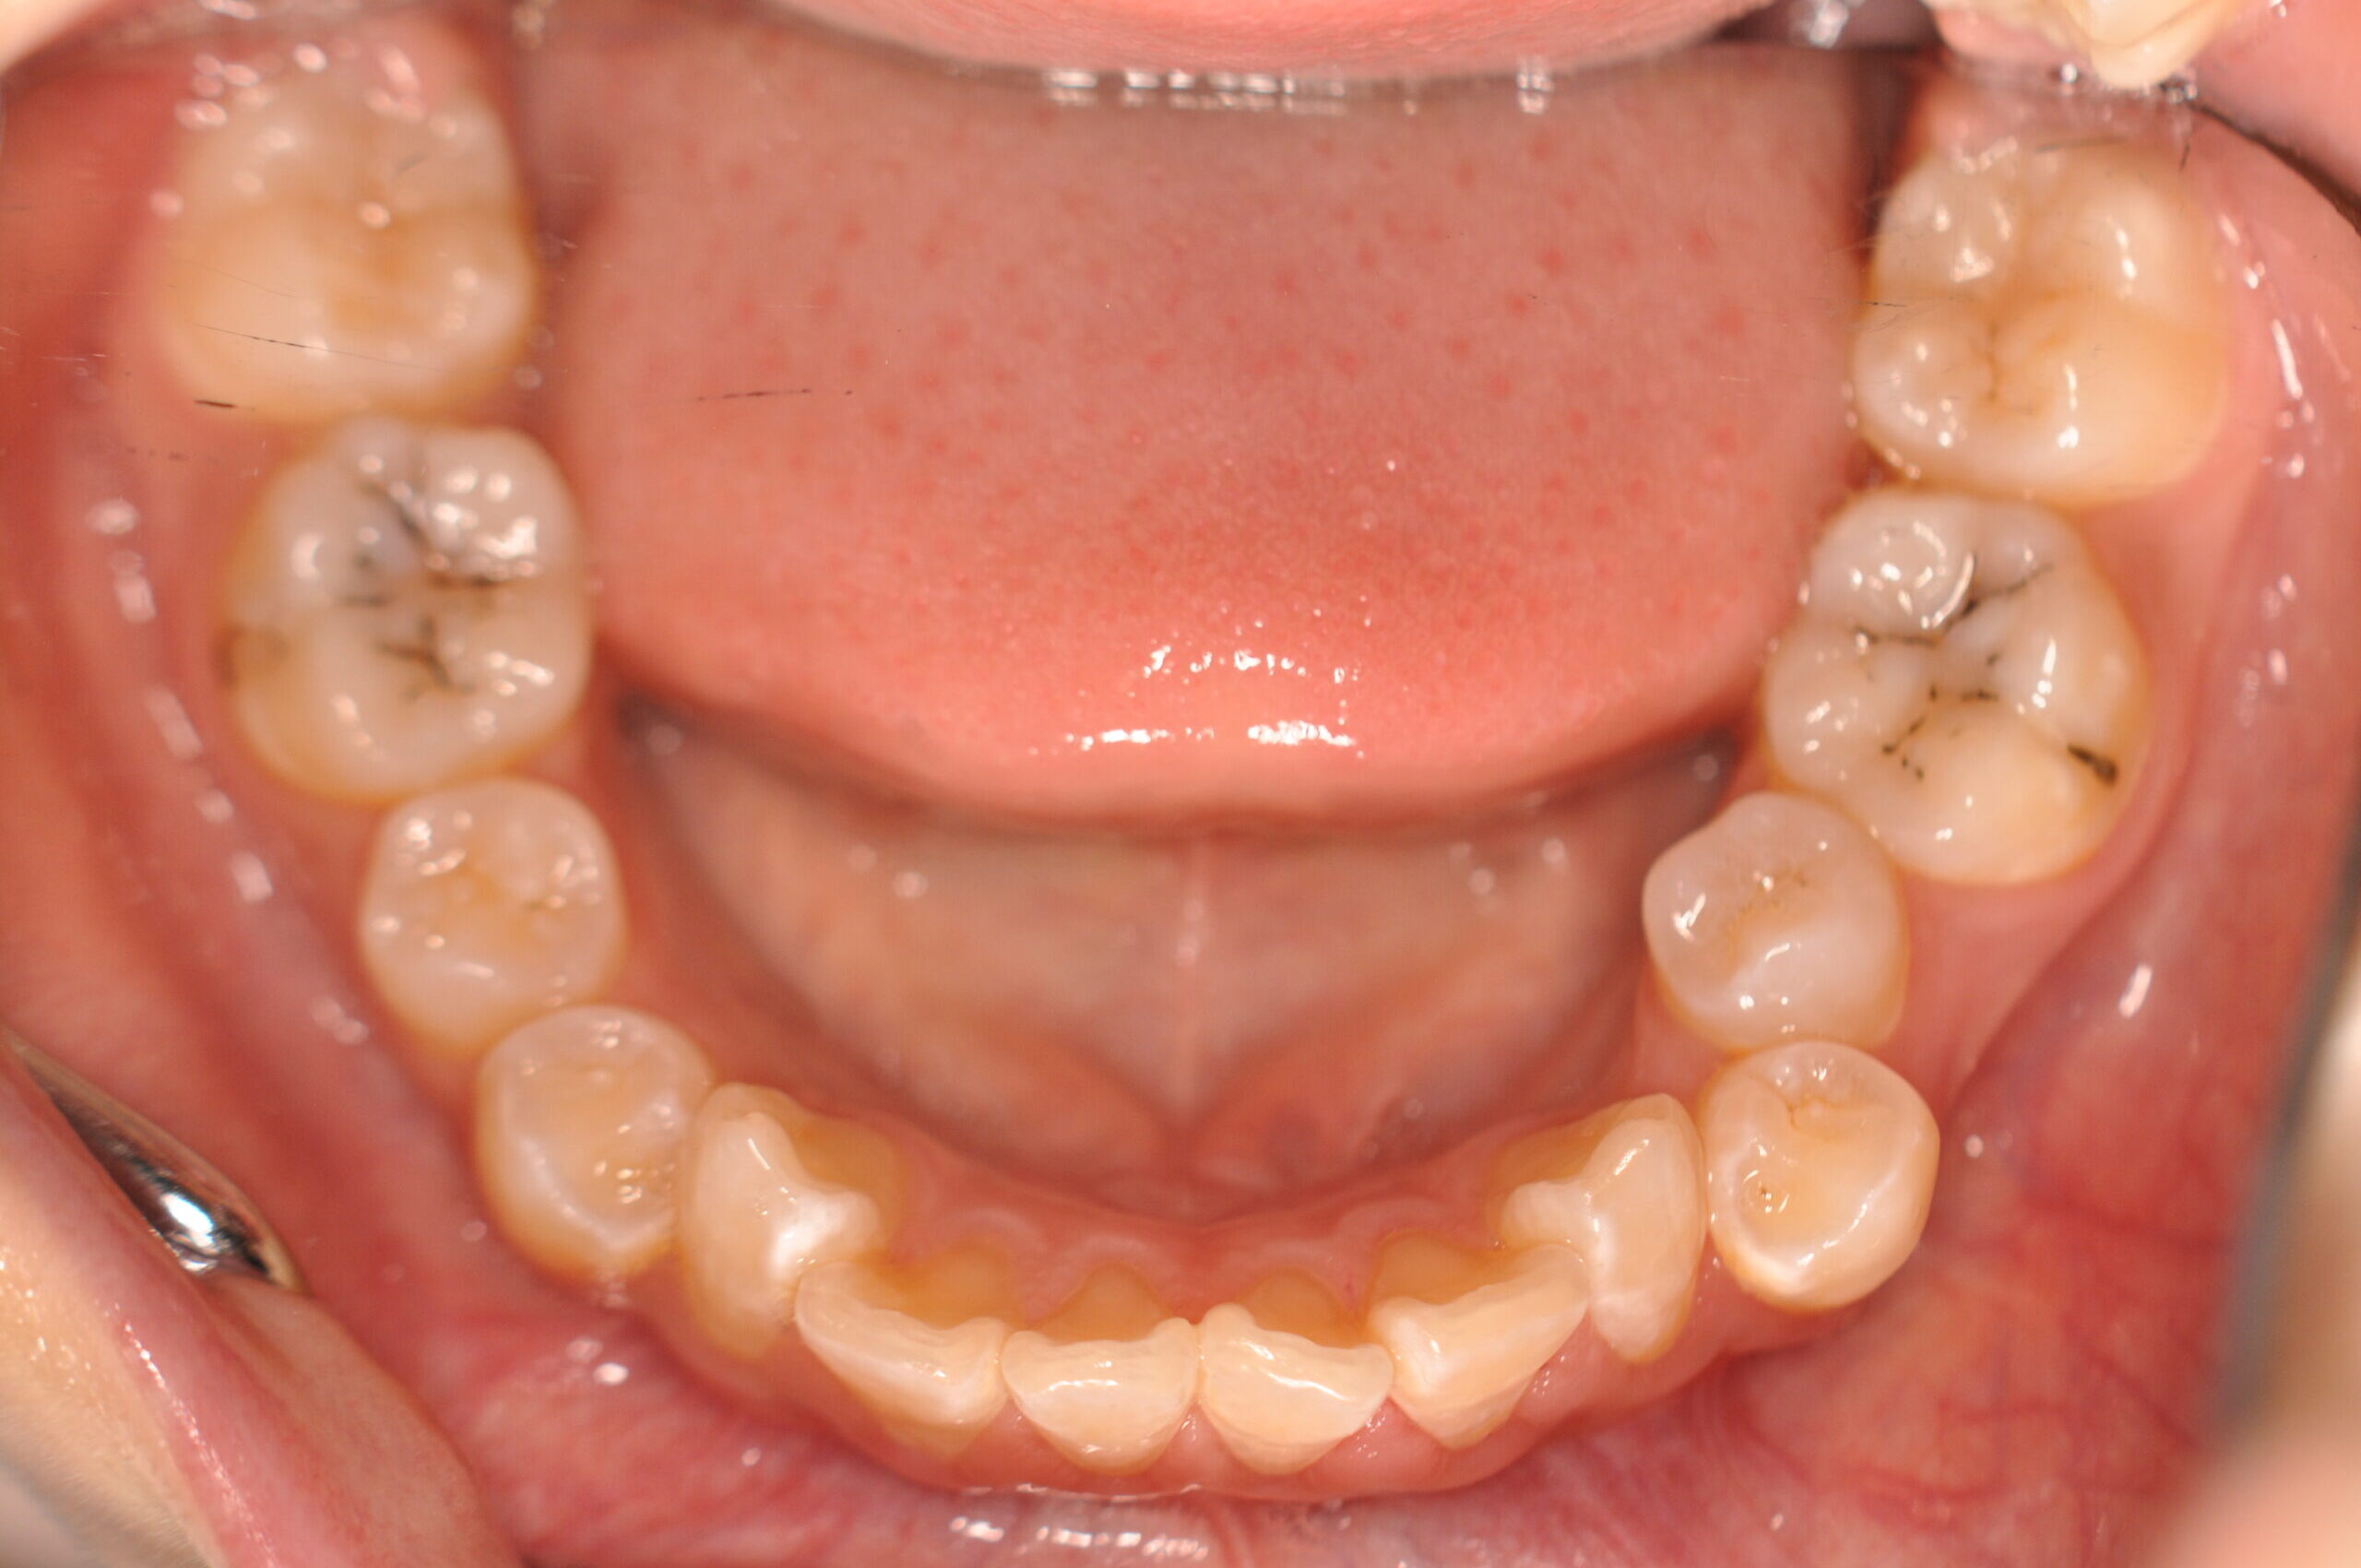

| 治療内容の詳細 | 初診時12歳の女性で、歯並びが悪く歯が磨きにくいことを気にされ来院されました。 検査の結果、上顎前突及び上下顎前歯部叢生を伴うアングルⅡ級1類不正咬合と診断しました。 治療としては、上顎左右第1小臼歯を抜歯し、セルフライゲーションブラケット装置(デーモンシステム)で歯の配列を行いました。 同時に顎間ゴムにて咬合関係の改善を行いました。 治療期間は、2年6ヶ月でした。 |